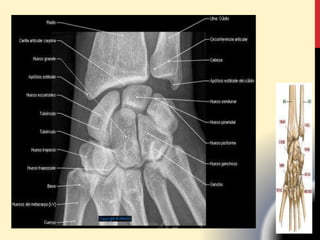

CARPO

TABAQUERA ANATÓMICA La tabaqueraanatómica es una depresión triangular en la región radial dorsal de la mano al nivel de los huesos del carpo, específicamente el escafoides y el trapecio. El nombre proviene del uso de su superficie para poner tabaco . La tabaquera anatómica es una región clínica destacada. EI pulso de la arteria radial también se puede captar en la tabaquera anatómica. Tabaquera Anatómica,  Hacia afuera el extensor corto del pulgar,  Hacia adentro el extensor largo del pulgar,  Conteniendo el escafoides, 1er y 2do N.radial y la arteria radial